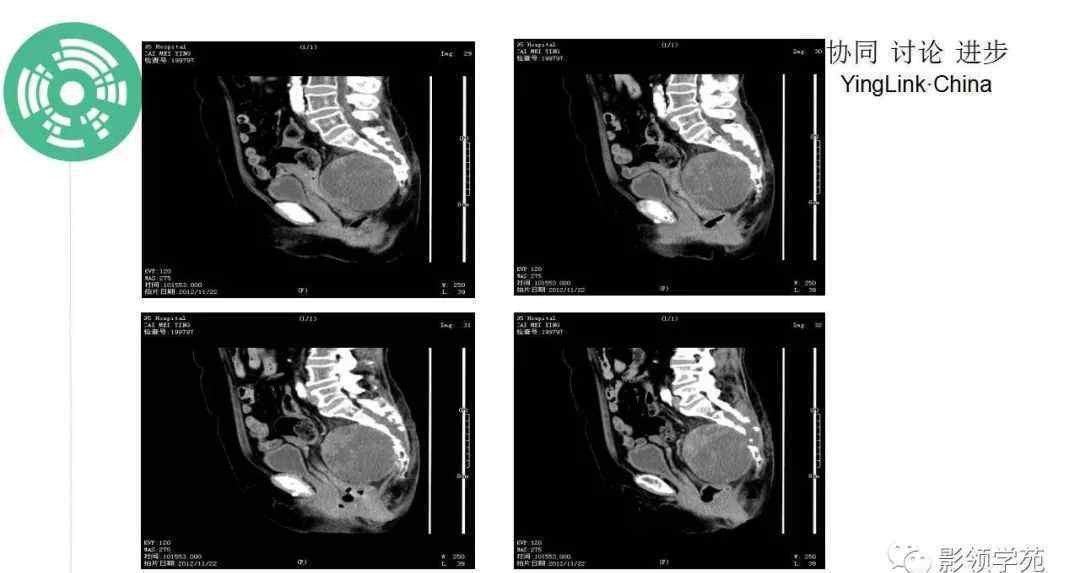

CT:一般表现为溶骨性膨胀性骨质破坏,常伴有软组织肿块,穿插斑片状钙化(钙化率低于软骨肉瘤),少数边缘表现为骨质硬化。